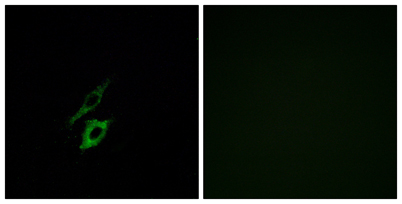

| Dilutions: | Western Blot: 1/500 - 1/2000. Immunofluorescence: 1/200 - 1/1000. ELISA: 1/40000. Not yet tested in other applications. |

| Cellular localization: | Cell membrane ; Multi-pass membrane protein . Internalizes in presence of its ligands, fMLP, TAFA4 and CTSG. . |